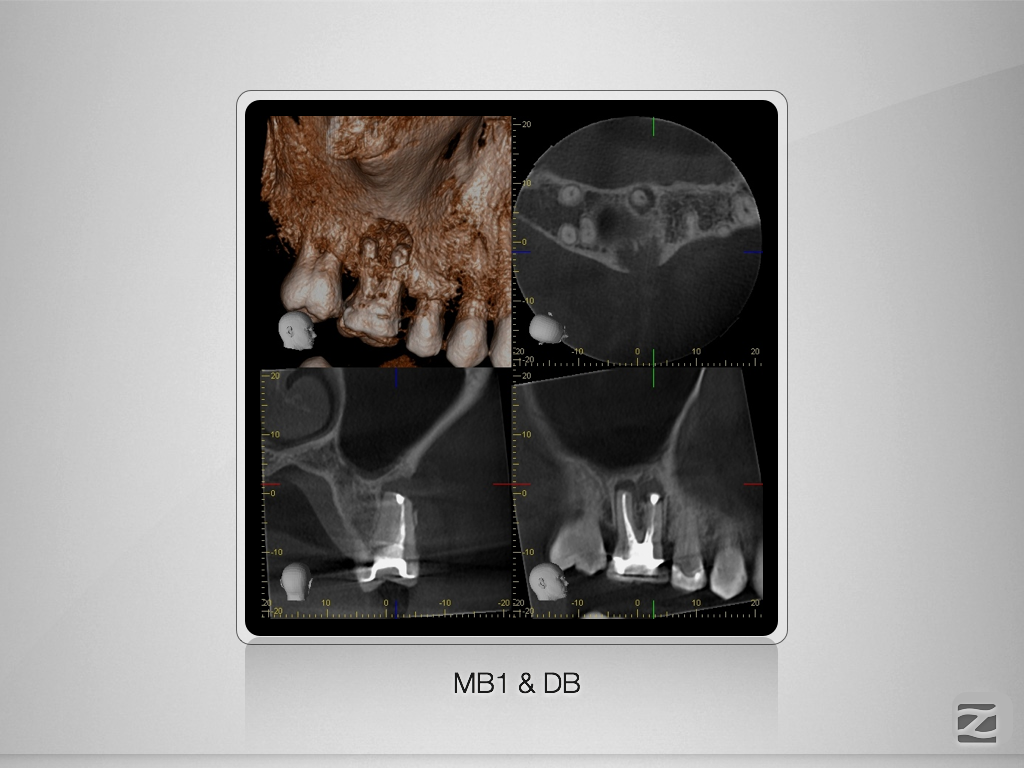

16D.004

1024 × 768

X-Bein/H-förmiger Isthmus/tiefer Split